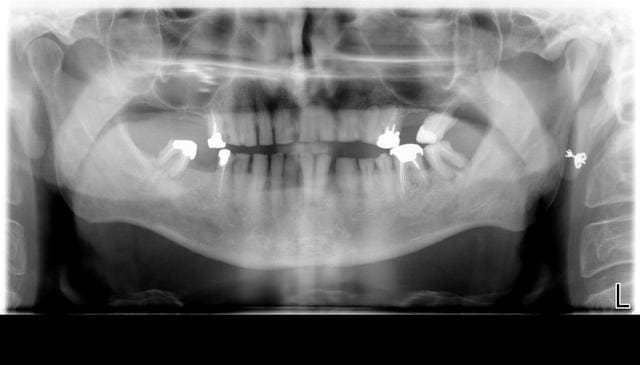

Vous trouverez ci dessous les photos des modèles d'étude (les photos sont pas terribles dslée) et la pano (27,37 et 47 ayant été extraites depuis).

En gros il a souffert de malnutrition enfant, les dents ne sont pas cariées mais super abrasées malgré une béance importante. D'ailleurs quand il ferme c'est instable car il peine à trouver un contact au niveau des prémolaires.

Donc ce que je pense lui proposer c'est implants à l'arrière pour les 6 à la mandibule (avec extraction de 36 préalable) et endo- Ic- couronne sur tout le reste. Comme il n'y a presque plus d'os sous les sinus j'envisage des extensions pour remplacer les 6 en solidarisant tout l'ensemble.

Du coup je ne remplacerais pas du tout les 7.

Je garde cependant une réticence à l'idée de faire des éléments en extension malgré la possibilité de s'appuyer de 5 à 5.